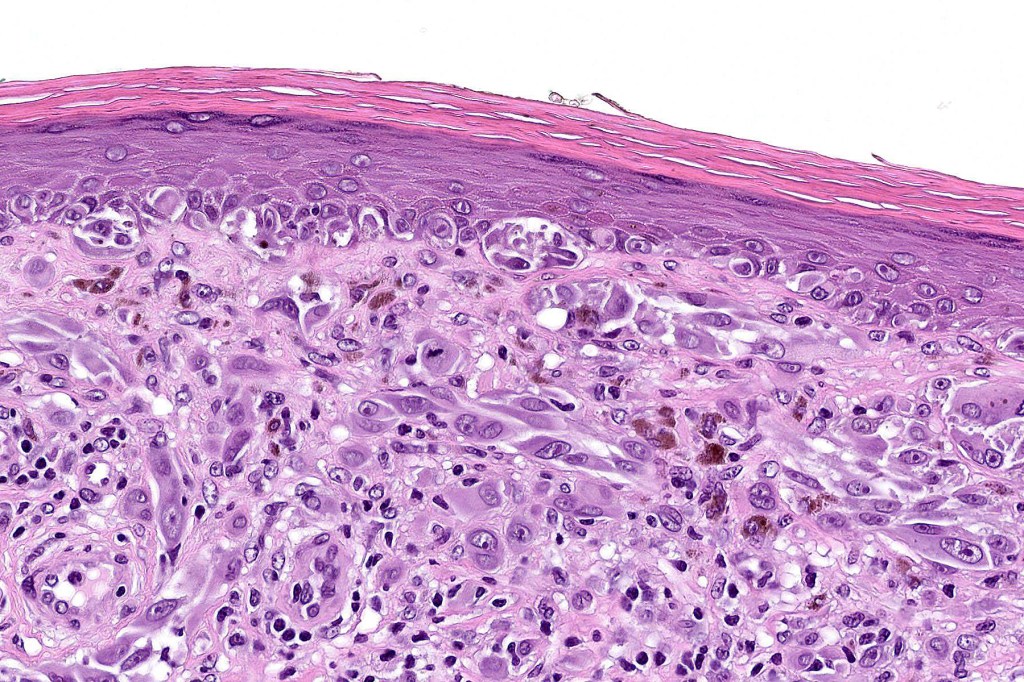

Histological features

•May show effacement/consumption of epidermis or ulceration

•Peripheral Pagetoid spread

•Large nodules which often show impaired maturation

•Loss of gradient with HMB45 and Ki67